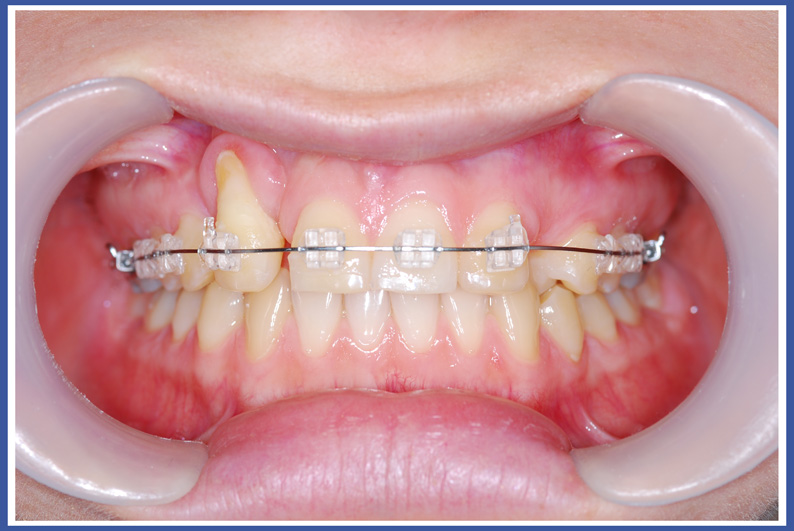

Ортодонтические брекеты (мост):

Это на сегодняшний день наиболее распространенное приспособление для выпрямления зубов. Брекеты приклеиваются к зубам, и проволочка, проходящая между ними, позволяет смещать зубы во всех трех измерениях при полном контроле над смещением, в отличие от пластинок, которые могут изменять только угол расположения зубов относительно челюсти. Брекеты могут быть как металлическими, так и прозрачными.

Брекеты, приклеиваемые к зубам, обладают многими преимуществами, но у них есть также и недостатки. Основной недостаток – это накопление остатков пищи и появление на нем микробов. Чтобы избежать опасности появления кариеса (дырок), нужно тщательнейшим образом чистить зубы в период лечения, и, насколько это возможно, избегать употребления пищи, ускоряющей развитие кариеса (пищи, богатой сахаром).

Инструкции для соблюдения гигиены рта во время ортодонтического лечения, выполняемого с помощью брекетов (моста):

Очень важно чистить пространство между зубами и кольцами, потому что микробы имеют тенденцию находиться в труднодосягаемых местах. Это действие предотвратит появление проблем и кариеса после завершения лечения и снятия брекетов.